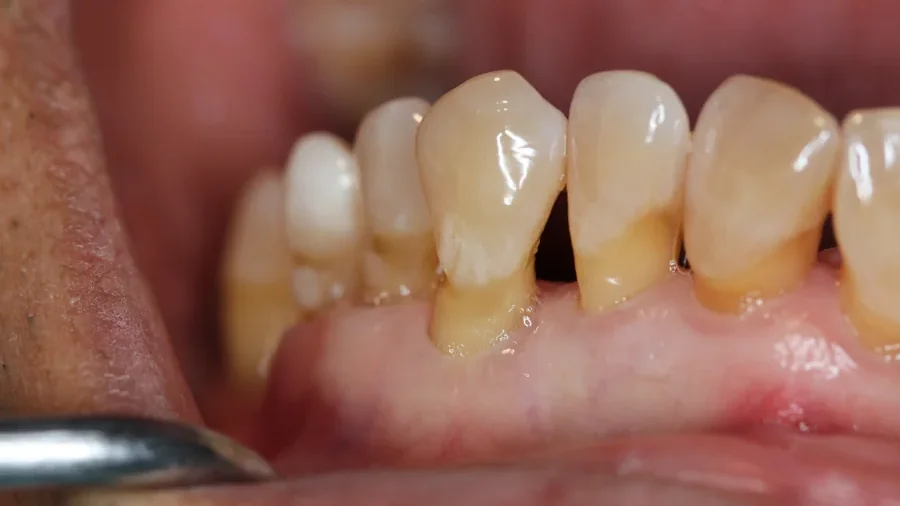

Zahnfleischrückgang oder Zahnfleischschwund bezeichnet den Prozess, bei dem sich das Zahnfleisch allmählich von den Zähnen zurückzieht. Dabei liegen die empfindlichen Zahnhälse zunehmend frei, oft sichtbar, manchmal auch schmerzhaft. Diese Veränderung wird in der Zahnmedizin als Gingivarezession bezeichnet.

Typisch ist, dass die Zähne im Laufe der Zeit länger erscheinen und sich kleine Spalten oder schwarze Dreiecke zwischen den Zähnen bilden. Viele Betroffene berichten auch von Kälteempfindlichkeit oder einem „Ziehen“ beim Zähneputzen.